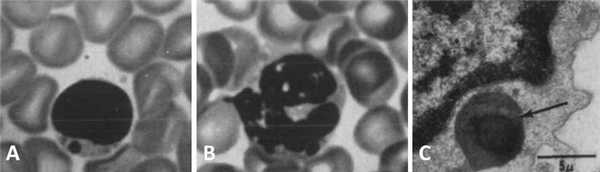

Чтобы более наглядно описать происходящие процессы при данном заболевании, еще во второй половине прошлого столетия была предложена оригинальная модель «бежевой мыши». Вследствие мутации в определенном гене (в то время конкретная точка генома, разумеется, не была известна) пигментация экспериментальной мыши изменялась, и исследователи определили ее цвет как «бежевый» («beige»). Помимо цвета у таких животных имелся еще ряд аномалий в виде огромных гранул меланина в лимфоцитах, нейтрофилах и эозинофилах (рис. 1), также подобные включения наблюдались в ряде других клеток [3].

Рисунок 1 | Периферическая кровь бежевой мыши. Световая микроскопия: определяются гранулы в цитоплазме лимфоцита (А) и нейтрофила (В). Электронная микроскопия: объемная гранула с темным содержимым в цитоплазме лимфоцита. Относится к непостоянным аномальным включениям [3].